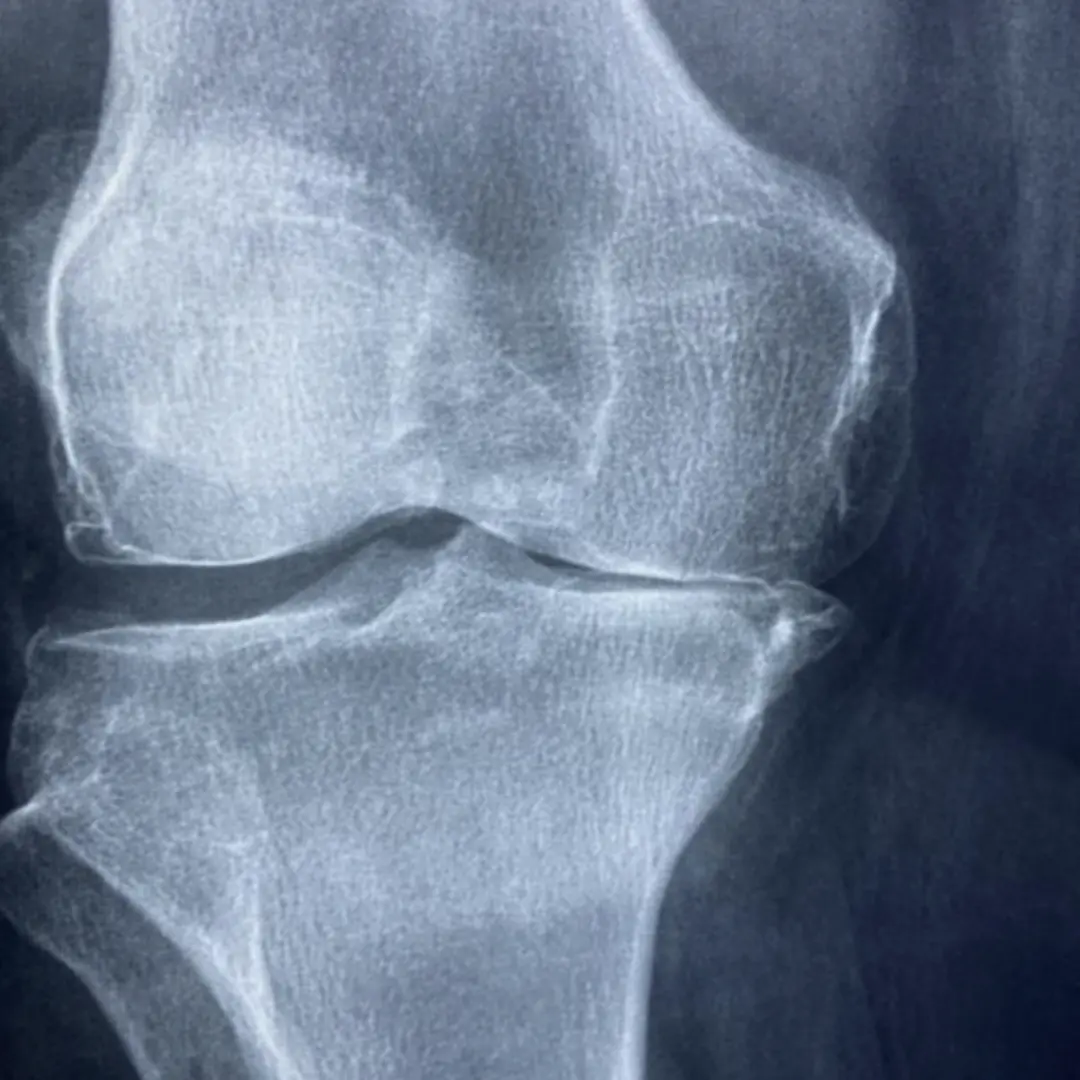

무릎 연골이 손상되면 다양한 증상이 나타날 수 있어요. 초기에는 뻐근하거나 욱신거리는 정도의 통증이 느껴질 수 있습니다. 특히 활동 후나 운동 후에 통증이 심해지는 경향이 있어요. 시간이 지나면서 무릎을 움직일 때마다 '뚝' 또는 '사각'거리는 소리가 날 수 있습니다. 이는 손상된 연골 조각이 관절 내에서 움직이며 발생하는 마찰음일 수 있습니다.

또한, 무릎이 붓거나 열감이 느껴질 수도 있어요. 관절액이 과도하게 분비되어 염증 반응이 나타나는 것이죠. 심한 경우에는 무릎을 완전히 펴거나 구부리기 어려워질 수 있습니다. 특정 각도에서 통증이 더욱 심해지거나, 무릎에 힘이 풀리는 느낌을 받을 수도 있습니다. 계단을 오르내리거나 앉았다 일어설 때 통증이 심해지는 것도 무릎 연골 손상의 주요 증상 중 하나입니다. 이러한 증상들은 일상생활에 큰 불편함을 초래할 수 있으므로, 주의 깊게 살펴볼 필요가 있습니다.

무릎 연골 손상의 원인은 다양합니다. 가장 흔한 원인 중 하나는 퇴행성 변화로 인한 관절염이에요. 나이가 들면서 연골이 점차 닳아 없어지기 때문이죠. 과도한 운동이나 무리한 활동 또한 연골 손상의 주요 원인이 될 수 있습니다. 특히 반복적인 충격이 가해지는 운동이나 갑작스러운 방향 전환은 연골에 부담을 줄 수 있습니다.

스포츠 외상으로 인한 직접적인 충격도 연골 손상을 유발할 수 있습니다. 축구, 농구 등 격렬한 운동 중 무릎 부위에 가해지는 강한 충격은 연골 파열로 이어질 수 있습니다. 이 외에도 비만으로 인한 무릎의 과부하, 잘못된 자세, 유전적인 요인 등이 복합적으로 작용하여 연골 손상을 일으킬 수 있습니다. 드물게는 감염이나 자가면역 질환이 연골 손상의 원인이 되기도 합니다. 따라서 정확한 원인을 파악하는 것이 중요하며, 이를 통해 적절한 치료 및 관리 방법을 찾을 수 있습니다.